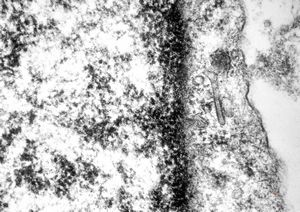

M,41y. | hairy cell leukemia - spleen - ribosome-lamella complex in tricholeukocyte